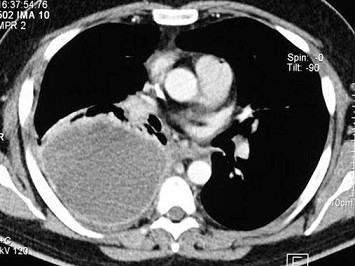

男,59岁,呼吸困难,胸痛,有发热,结合CT图像,最可能的诊断是()

A.脓胸

B.肺脓肿

C.大叶性肺炎

D.肺囊虫病

E.肺癌